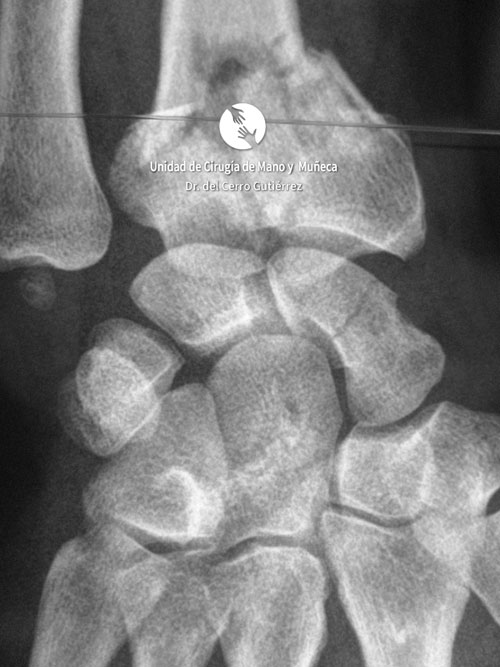

Imágenes de diagnótico de fracturas del radio distal de la muñeca

Las imágenes de diagnóstico son fundamentales para evaluar las fracturas del radio distal, identificar su gravedad y definir el tratamiento más adecuado. A continuación, presentamos una serie de ejemplos que muestran diferentes tipos de fracturas.

Fractura del Radio. Fractura Extraarticular